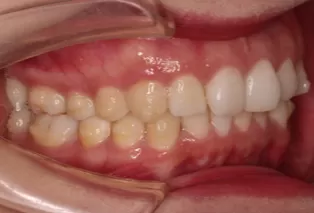

Intraoral photos